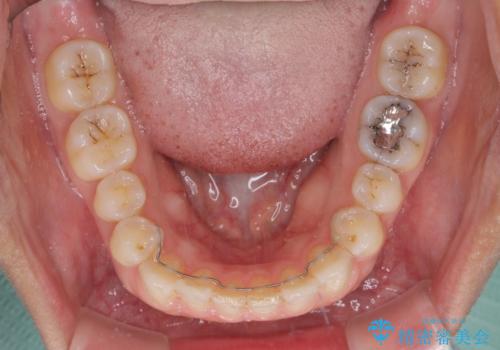

舌癖を改善したことで、隙間や突出感を改善することができました。

隙間は後戻りしやすいため、舌側を細いワイヤーで固定することとしました。